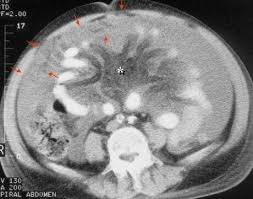

Final Diagnosis Right Subphrenic Intraperitonal Encapsulated Csf Csf Pseudocyst Collection Containing The Distal Ventriculoperitoneal Catheter Abdominal Cysts